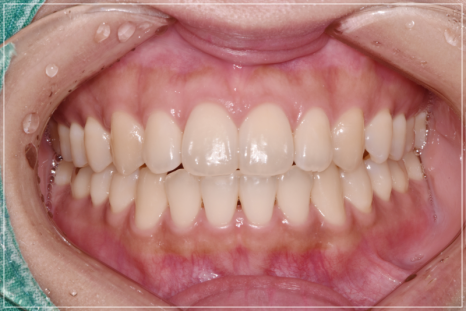

입이 안 다물어지는 문제를 해결한 모습

입술이 붕 뜨는 고민을 해결한 모습

앞니가 안 다물어지는 상태를 개선한 모습

가지런히 정돈된 치열과 개방교합이 개선된 모습